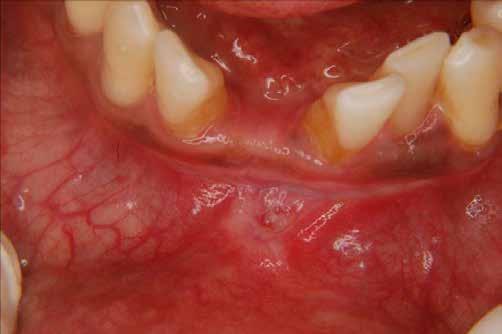

A parodontális elváltozások kezelésének elengedhetetlen része, hogy a páciens a kezelés teljes ideje alatt megfelelően együttműködjön a beavatkozásokat végző fogorvossal, és pontosan kövesse az utasításait. A megfelelő kooperáció elősegítése érdekében javasoljuk, hogy a kezelés minden fázisában egy intraorális szkenner (pl.: Condor; Biotech Dental) segítségével készült, 3 dimenziós modell segítségével ismertessük a páciensünkkel a szájüregi státuszának aktuális állapotát (2. ábra)

Az első találkozás alkalmával a kezelést igénylő terület állapotát egy intraorális szkenner segítségével rögzítjük. Ez a képalkotó eljárás kiegészíti azokat az általánosan alkalmazott vizsgálatokat, mint a radiológiai képalkotás (3. ábra) és a parodontális státuszfelvétel (4. ábra), továbbá hozzájárul a pontos diagnózis felállításához.

A kezelés e szakaszának a befejezésekor a gyulladásos tünetek hiánya, a csökkenő tasakmélység és a szondázást követő vérzés megszűnése megfelelő bizonyítékul szolgálhat az eddig elvégzett beavatkozások hatékonyságára (15. ábra). A páciensek idővel képesek lesznek ennek az állapotnak a fenntartására, ha a fogorvosok által adott instrukcióknak megfelelően végzik a napi szájhigiénés tevékenységüket, és ha ebben megfelelően támogatják őket.

Ebben a fázisban alapvető fontosságú, hogy bemutassuk a páciensnek a kezelés során elért eredményeket, mivel ezzel tudjuk őt leginkább arra motiválni, hogy fenntartsa az elért, megfelelő szájhigiéniás állapotot, továbbá, hogy rendszeresen megjelenjen a jövőben tervezett kontrollvizsgálatokon. A megfelelően kivitelezett LAFMD protokoll befejezésekor, a páciensünk is megfigyelheti, hogy sem gyulladásos tüneteket, sem vérzést nem tapasztal, valamint érezheti a lágyrészek stabilitásából és a megfelelő szájhigiéniás státuszból fakadó előnyöket (16. ábra). A Condor intraorális szkennerel készített színes, háromdimenziós modellek kiválóan alkalmasak a szájüregi státusz bemutatására, továbbá a páciens hatékony motivációjának elősegítésére.